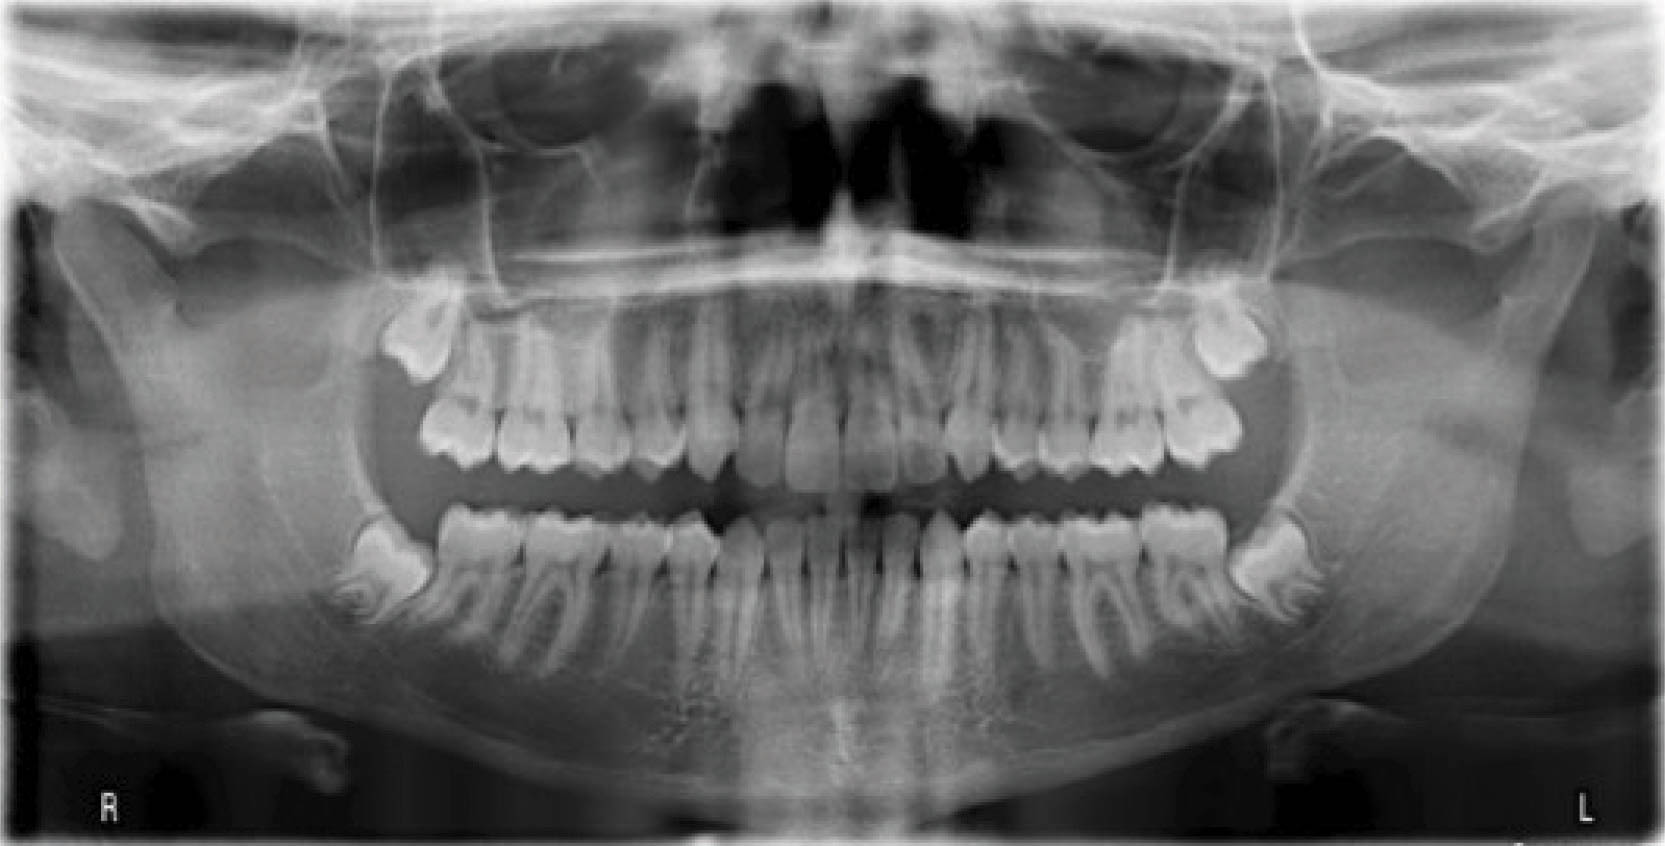

یک بیمار ۱۴ ساله دختر با اکلوژن و دیپ بایت به همراه کرادینگ قدامی بالا و پایین (شکلهای 60-6 الی 62-6).

شکل 60-6

شکل 61-6

شکل 62-6

به تصاویر پایان کار نگاه کنید (شکل 63-6) که کرو اسپی با کمک اتچمنتها و انکوریج صحیح صاف شده است. انسیزورهای بالا اینترود شدند تا طرح لبخند زیباتر شود. در تصاویر صورتی قبل و بعد از کار (شکلهای 64-6 و 65-6) میزان نمایش لثه خیلی کم شده و طرح لبخند هم قشنگتر است.

عکس OPG پایان کار (شکل 66-6) طبیعی است. سوپرایمپوز نمودن لترال سفالومتریها (شکل 67-6) پروترود شدن انسیزورهای پایین را نشان میدهد که هم برای رفع کرادینگ و هم برای اینترود نمودن نسبی قدامیها مفید بود.